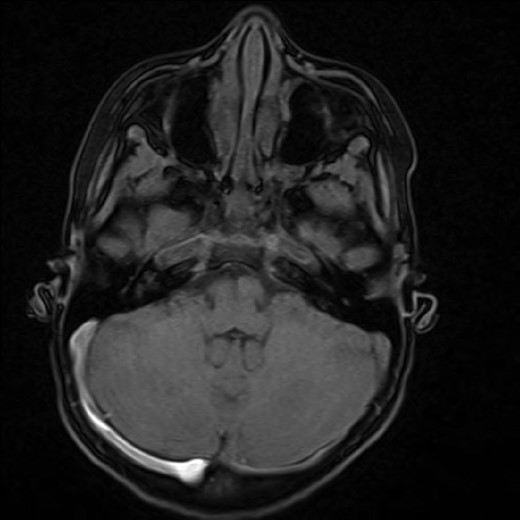

A 12-year-old girl presented with a 7-month history of frontal headaches and intermittent left-sided proptosis. On examination, she had dilated and engorged scleral veins on the left eye (evident on inspection), mild dysdiadochokinesia and past pointing on the left side. A brain computed tomography (CT) with contrast showed an enlarged left superior ophthalmic vein and a prominent left cavernous sinus. An interventional radiography (IR) cerebral angiogram under general anaesthesia was performed, which revealed evidence of an indirect CCF fed by ophthalmic branches of the left internal carotid artery and filling from multiple ethmodial branches of the distal internal maxillary artery. From the fistula, the ophthalmic vein was markedly hypertrophied and drained the cavernous sinus anteriorly. The fistula was also feeding from the right side through ethmodial branches into the right cavernous sinus and across to the left cavernous sinus (Fig. 2).

The patient was discharged 3 days later and a follow-up brain magnetic resonance imaging (MRI) was conducted 4 months afterward, which showed some residual proptosis. The superior ophthalmic vein was prominent but clearly less prominent than previous imaging. On a routine outpatient follow-up, her proptosis had significantly improved with reduction of the corneal injection, she reported no headaches and normal vision. A follow-up IR cerebral angiogram was conducted 4 months later that revealed no evidence of a residual CCF.